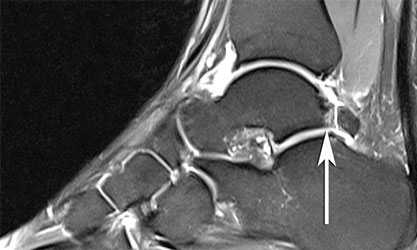

Рис. 3. МРТ ГСС, аксиальные сканы: 2 типа передне-латерального импинджмент-синдрома - фибриллярный и нодулярный.

УЗИ-семиотика: мягкотканные фиброзные массы в переднелатеральном пространстве голеностопного сустава - образование неоднородной эхогенности с бугристыми контурами, утолщение и неоднородный сигнал от передней таранно-малоберцовой связки

МРТ-семиотика

Т1-ВИ: скопление жидкости в переднелатеральном пространстве, фиброзная ткань выглядят гипоинтенсивными, свободные костные тела гиперинтенсивны;

Т2-ВИ, PD-FS: скопление жидкости в переднелатеральном пространстве выглядит гиперинтенсивным, фиброзная ткань изогипоинтенсивна; утолщение, разволокнение передней таранно-малоберцовой связки и/или связки Бассета - изогипоинтенсивный на PD-FS.